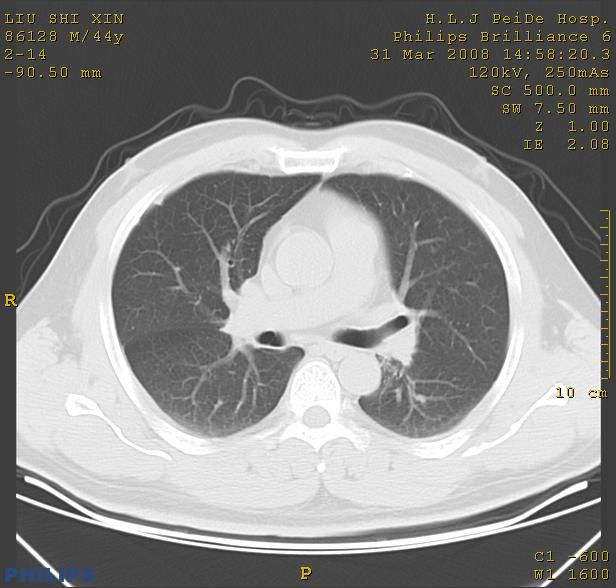

标题: CT13096:请分析胸膜下结节的影像基础是什么 有病理结果 [打印本页]

标题: CT13096:请分析胸膜下结节的影像基础是什么 有病理结果

瘢痕挛缩,胸膜牵拉,血管纠集扭曲,上叶前段支气管显示欠清,周围散在斑片影,以纵隔旁肺癌可能性大。请穿刺检查。

中心型肺癌并阻塞性肺炎及肺内转移

中心型肺癌并阻塞性肺炎、两肺及胸膜多发转移。

结节灶与血管末梢相通象转移灶;小三角状尖部有纤维索是胸膜拉扯征;纵隔旁大片实性影有点状钙化;周围有名显纤维瘢痕征可考虑瘢痕癌

胸膜下结节是转移了。

本病例有病理结果是,鳞状上皮癌,胸膜下结节影病现诊断的肿大淋巴结,谢谢大家分析,请问胸膜下结节是肿大淋巴结怎么解释